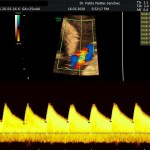

Modalidad de imagen ecográfica que permite evaluar flujos arteriales y venosos en estructuras fetales, placentarias y maternas obteniendo información valiosa sobre

- Riesgo materno para pre eclampsia severa (Evaluación de arterias uterinas)

- Riesgo fetal para cardiopatías congénitas y alteraciones cromosómicas (Evaluación de Ductus venoso).

Este modo ecográfico nos brinda datos importantes desde la 6ta a la 40ta semana de embarazo. Nosotros la utilizamos en todos nuestros exámenes ecográficos.